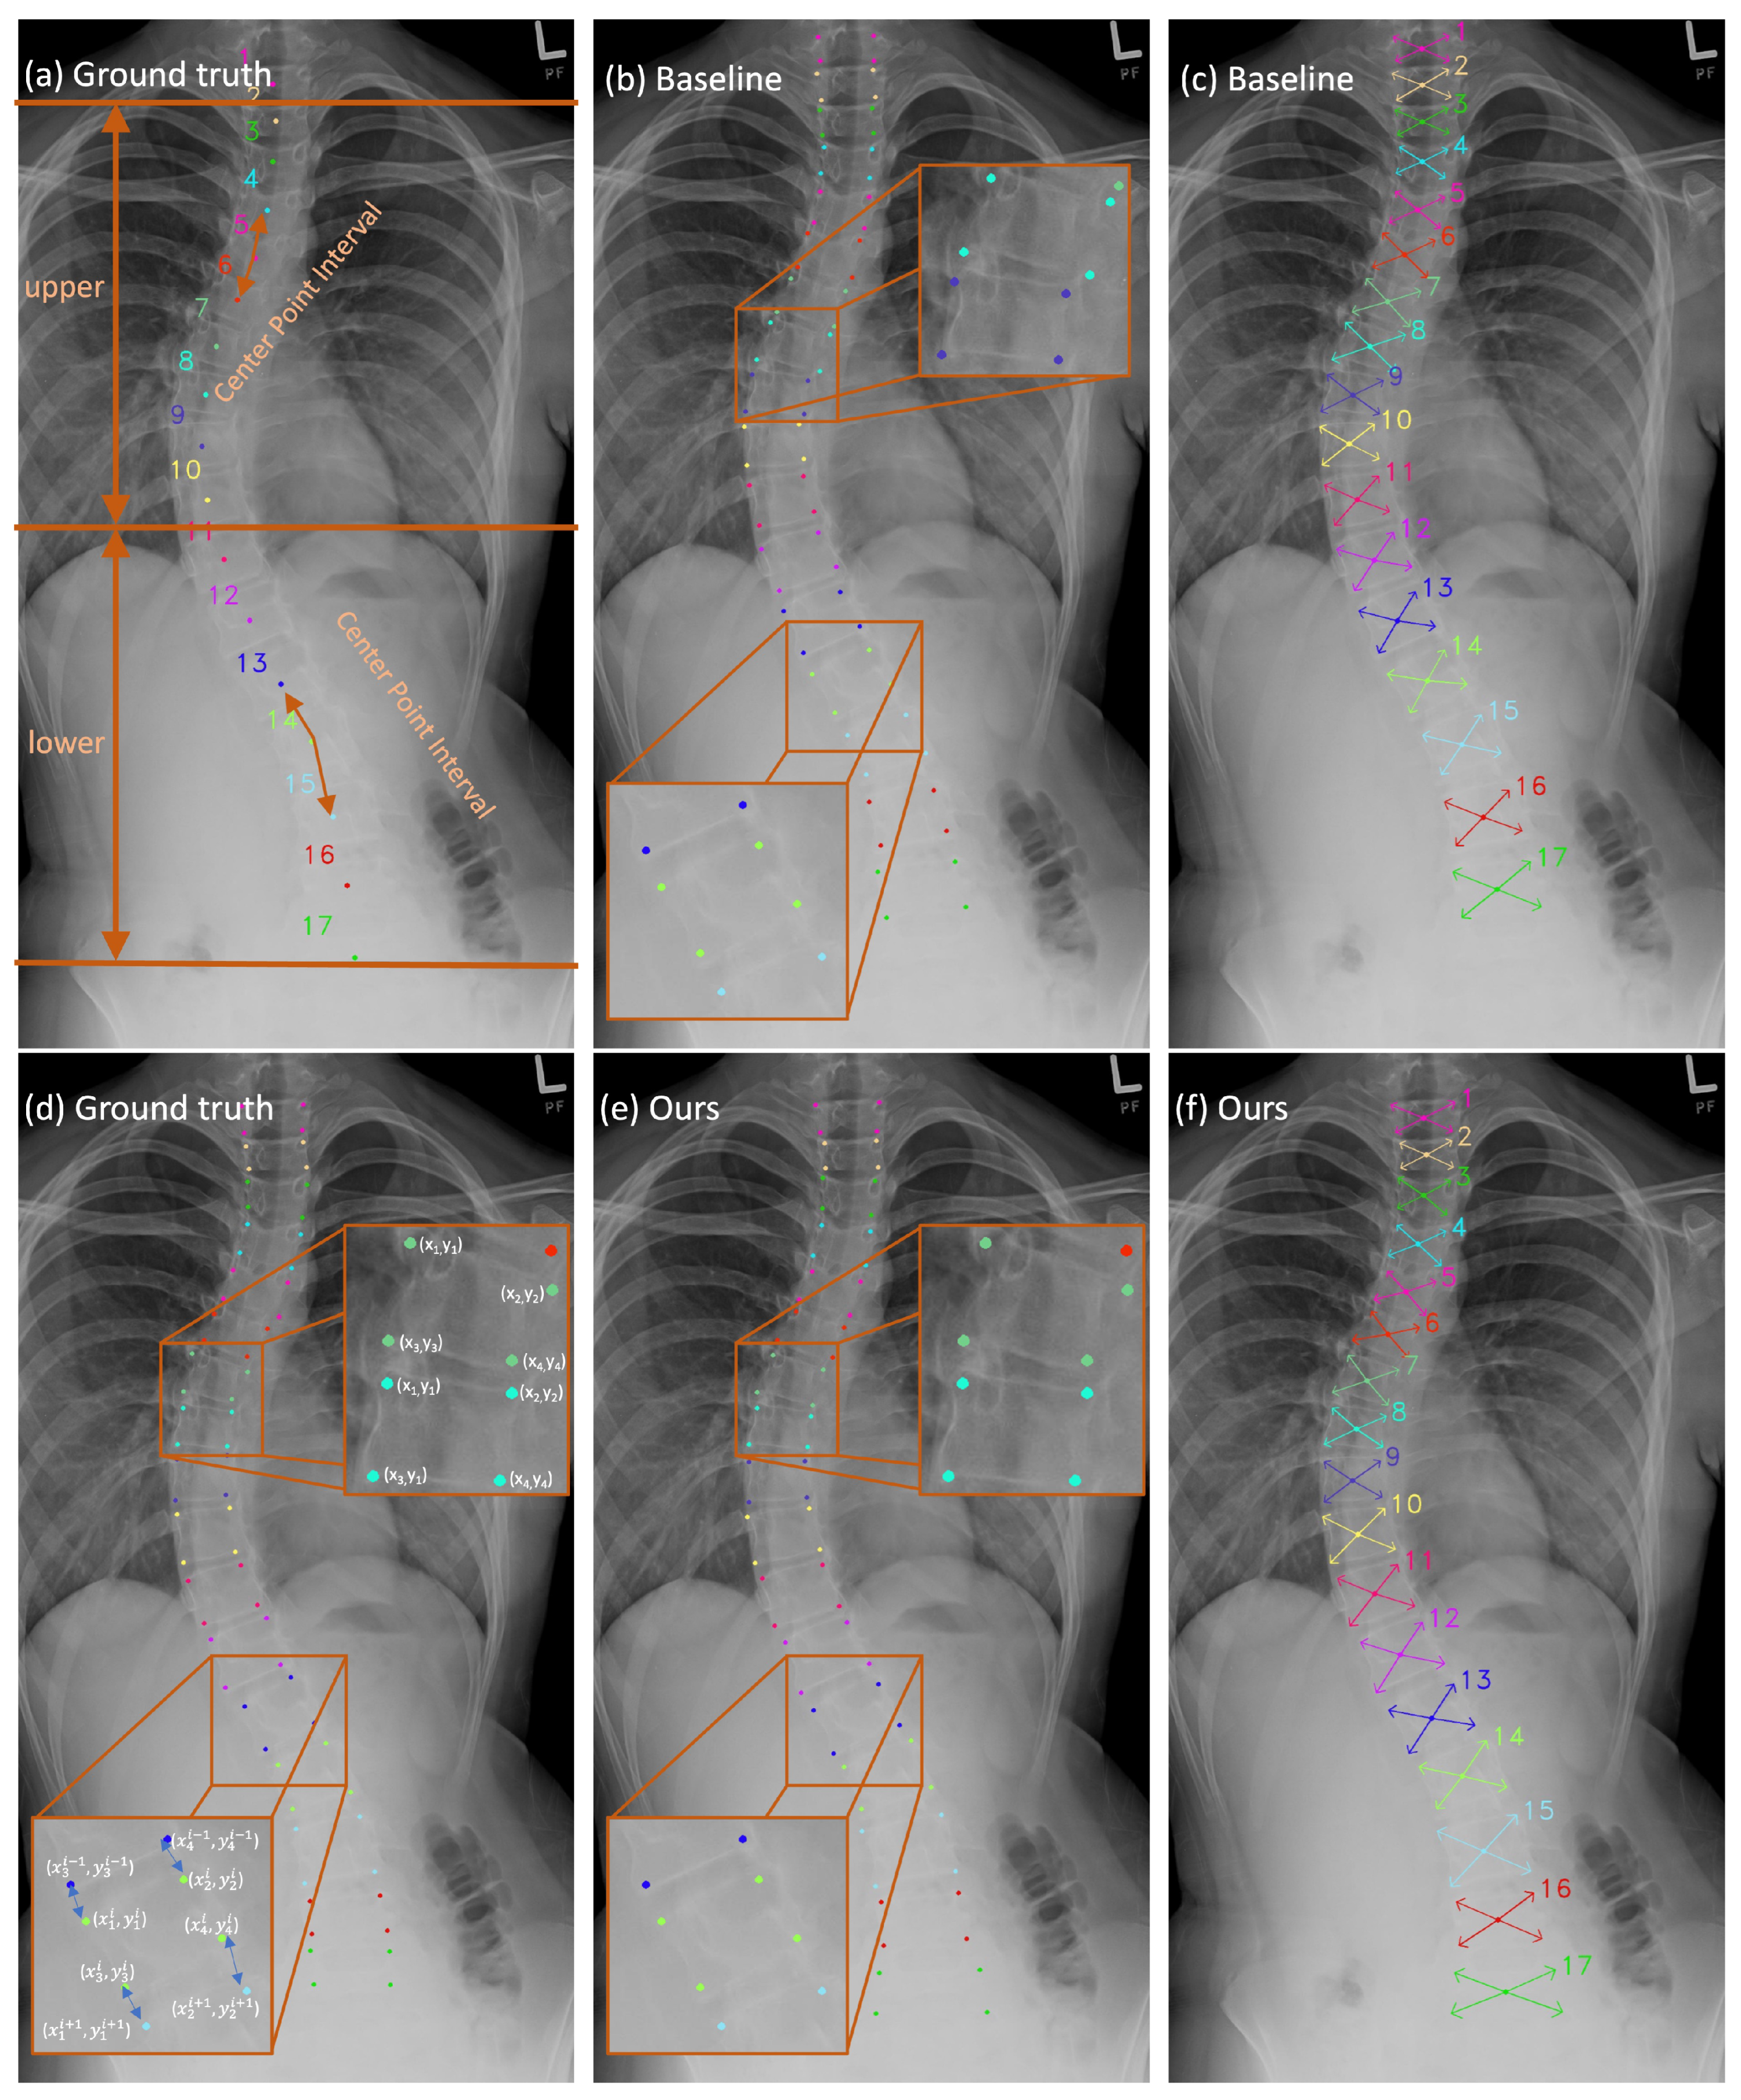

Figure 2.

The qualitative results in these figures are generated through the S2D-VLI VLDet model. (a,d) can be considered ground truths. (b,c) illustrate the outputs of the baseline approach [50] in terms of vertebra landmark detection. Meanwhile, (e,f) demonstrate the results of our approach to vertebra landmark detection.

The spine X-ray scan in Figure 2a reveals a distinct difference in background interference levels between the upper and lower regions of the spine. As seen in Figure 2a, the 17 vertebrae comprising the spine are divided into two separate groups based on the severity of background interference. The first group comprises the top ten vertebrae, while the second comprises the bottom seven vertebrae. This division is defined based on how severe the interference from the background is. The upper region background consists mainly of the lung, whereas the lower half is interfered with by the thoracic and abdominal cavities. Due to the density and morphology of the tissue and organ, the background interference is more severe in the lower half. As a result, it is more difficult to find the vertebrae in the lower part. The mean detection error (MDE), which is computed in pixels, can yield more precise quantitative findings for locating 17 center points and 68 landmarks. The results can be found in Table 1. The baseline approach yields a significantly higher MDE (approximately 50%) for center points in the lower region compared to the upper region, resulting in an overall MDE increase of approximately ten pixels for the entire 17-vertebrae spine. Meanwhile, the accumulation of errors in the localization of the center points will result in inaccuracies in the localization of the corner points. Consequently, this will lead to errors in the calculation of the Cobb angle, which is used for the assessment of scoliosis. As a result, to improve the precision of center point localization, we propose the CPIE approach, which incorporates adjacent center point intervals, which are indicated by double-sided arrows in Figure 2a. Once the additional pathway (CPIE pathway) is incorporated as a supplementary pathway following the decoder, it enables a comprehensive analysis of the correlation between the center points in neighboring vertebrae. This correlation actively contributes to the training process through the back-propagation process. Furthermore, by employing a multi-task learning scheme as a regularization strategy that incorporates an inductive bias [53], potential bias towards specific tasks during training is mitigated, thereby reducing the risk of overfitting [53].

The primary reason for the overall error results from the inconsistency between the predicted corner points and their practical location. Instead of being situated at the border corners of the vertebrae, the predicted corner points are found within the interior of the vertebrae, as shown in Figure 2b. It demonstrates that the estimated corner points obtained using the baseline method lack sufficient precision. The fact that the border between two neighboring vertebrae is not properly differentiated is a possible explanation for this finding that makes intuitive sense. Hence, it is essential to enhance the learning capacity of the network at the interface’s boundaries between two adjacent vertebrae. Giving the model as much supervision information on neighboring vertebra borders as it is physically possible to learn without incurring extra labeling costs is the optimal strategy for approaching this problem. As a result, we introduce the idea of using AVIE as one of the pathways after the backbone decoder. As shown in Figure 2d, the corner points of each vertebra are located in the sequence shown, which is clockwise. The offset is measured from the corner points (, ), (, ) of the upper vertebra to the corner points (, ), (, ) of the lower vertebra accordingly, as shown in Figure 2d. Throughout the whole training phase, the parameters of both estimators are optimized, making use of the L1 loss.

Figure 2 shows some qualitative findings on corner offset regression and landmark detection.